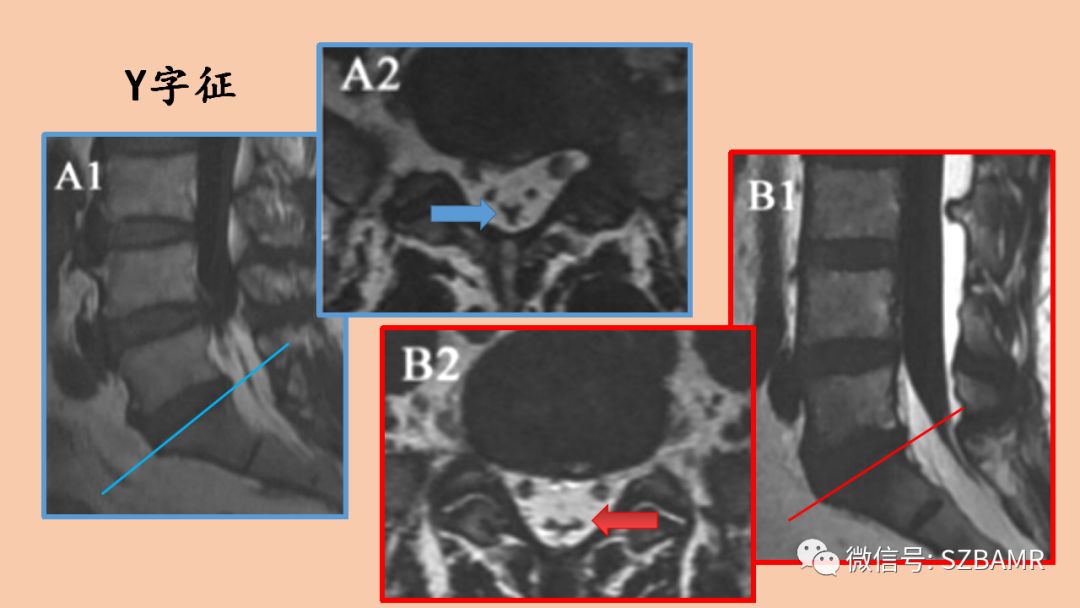

影像表现:胸椎通常堆积于椎管后方,腰椎包绕整个硬膜囊的脂肪信号,压迫硬膜囊,横断面上出现“Y字征”、“星形征”、“线征”或“椭圆征”。